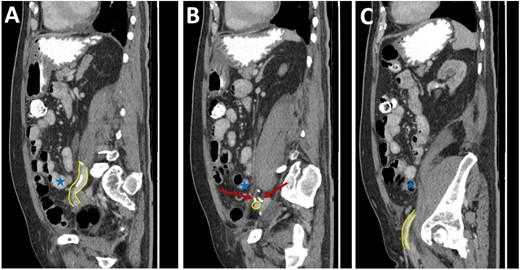

Three-dimensional reconstruction of the pre-operative (left) and post-operative (right) CT scan. The pre-operative CT demonstrates a segment of EIA that cannot be reconstructed due to the slow flow through the segment involved in the SBO (yellow arrow). The post-operative image demonstrates a patent EIA following vascular repair (blue arrow).